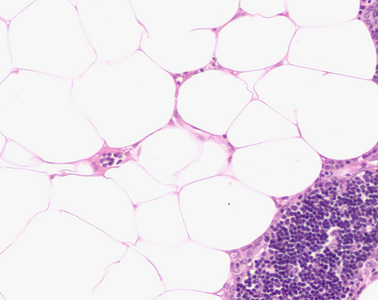

Präparat 13: Thymus (erwachsener Mensch), Gewebsschnitt, H.-E.

Im Mark befinden sich die auffälligen Hassall-Körperchen in verschiedenen Zustandsformen und Größen. Die Hassall-Körperchen bestehen aus modifizierten Retikulumzellen mit großem leerem Zellkern und sehr deutlichem Nukleolus, die sich zu Gruppen zusammenlagern. Dabei umgeben die äußeren Zellen des Hassall-Körperchens die inneren zwiebelschalenartig. In den größeren Körperchen findet sich im Inneren oft Zelldetritus in Form von intensiv basophilen Punkten oder unregelmäßig strukturierten azidophilen Verklumpungen.